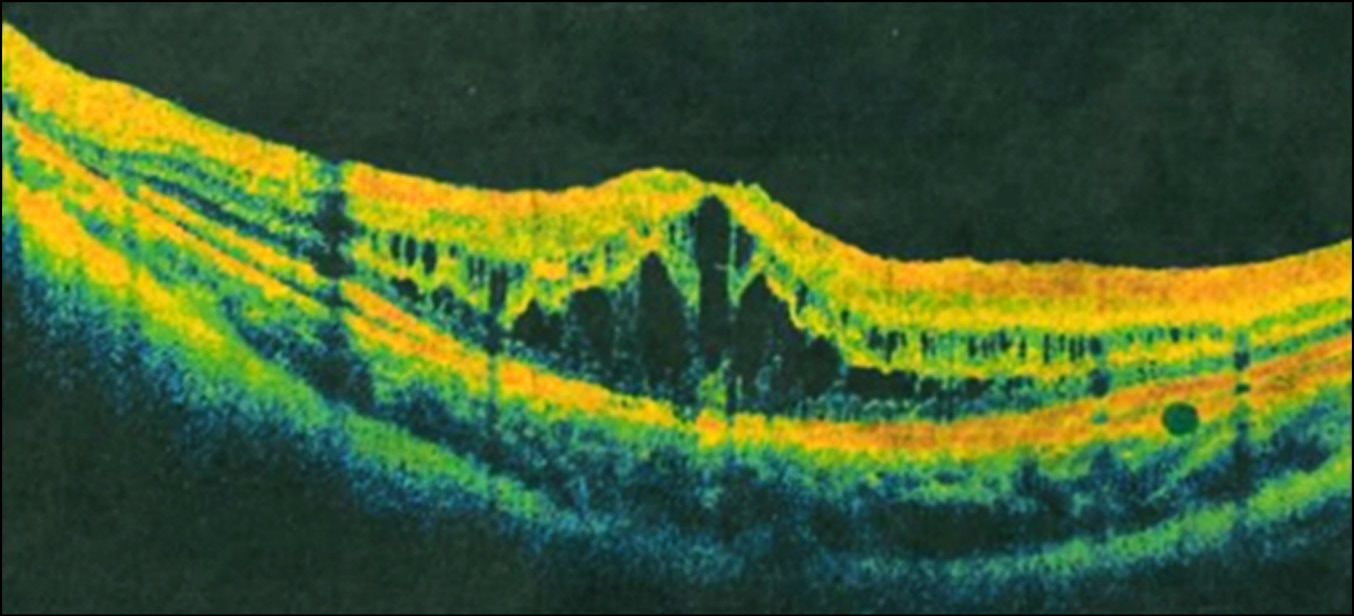

С помощью ОКТ выявлено значительное увеличение толщины сетчатки в макуле: ОД — 678 мкм, ОС — 651 мкм, что явилось свидетельством множественных кист в макулярной области (фовеошизис). На ОКТ-сканах хорошо видно, что образование кист и ретиношизиса происходит во внутреннем и наружном ядерном слоях (рис. 2).

Рис. 2. Макулярные кисты и ретиношизис по данным оптической когерентной томографии.

Fig. 2. Macular cysts and retinoschisis according to optical coherence tomography.